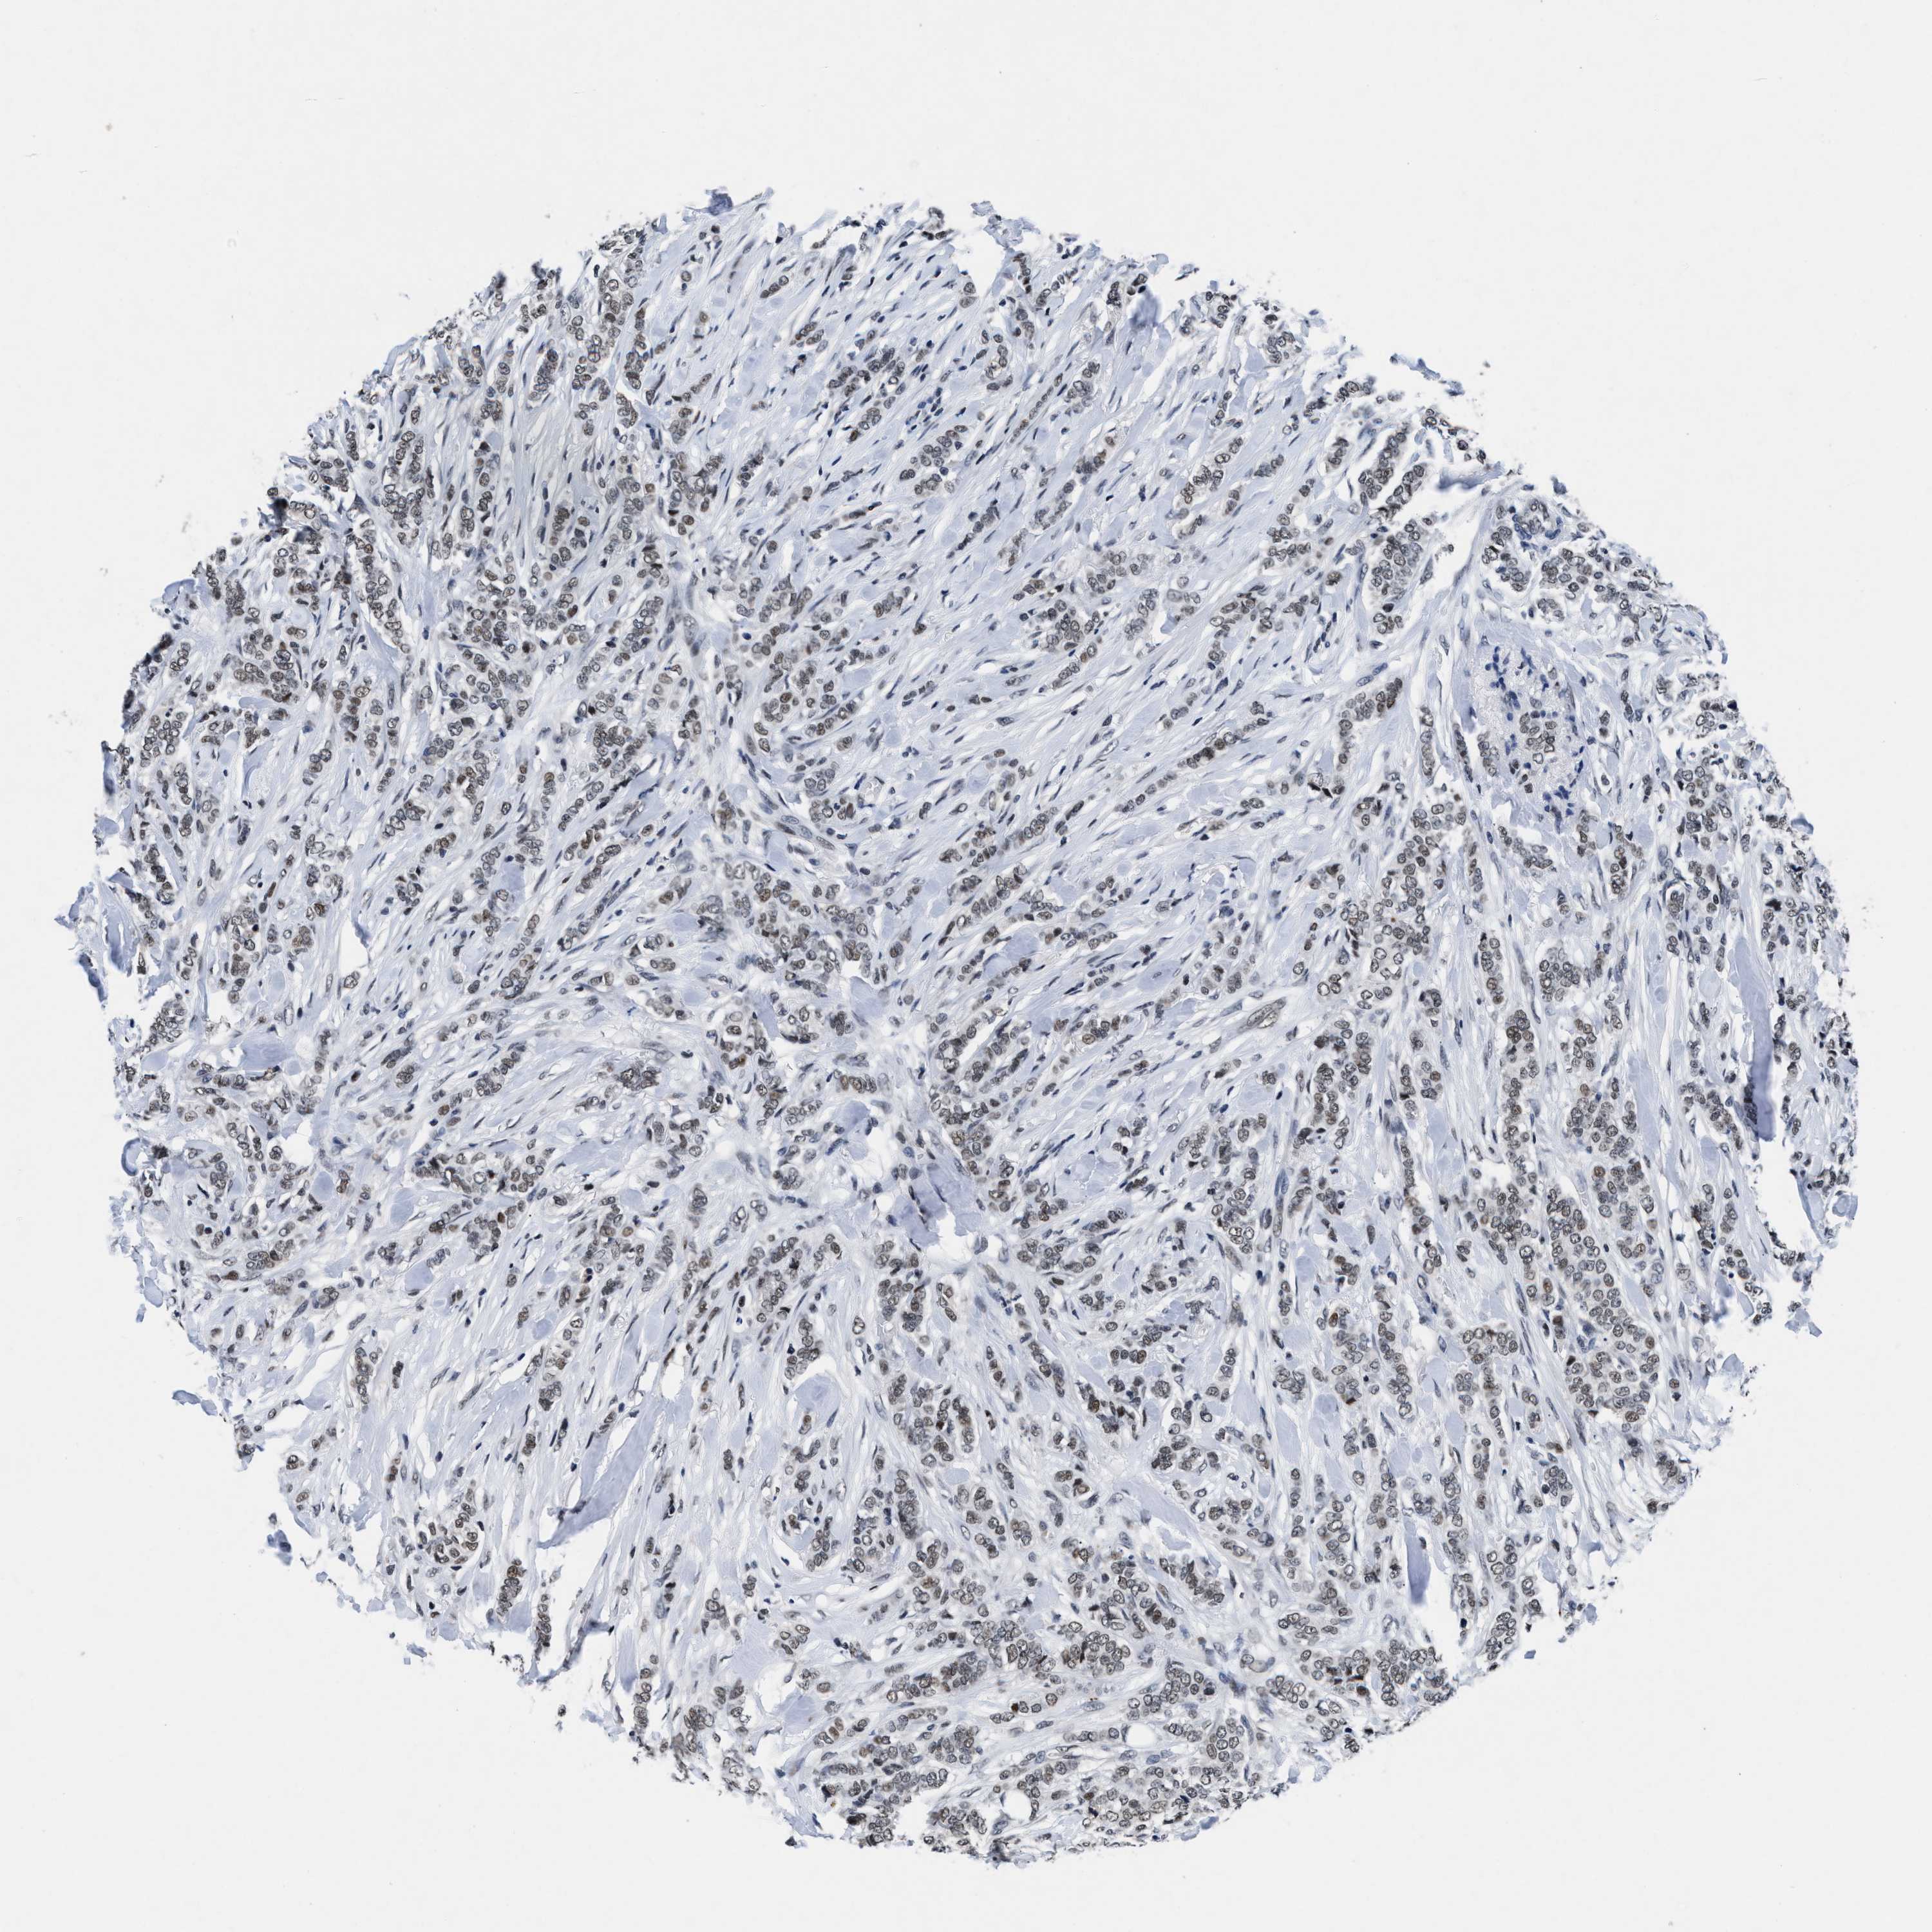

CANCER BREAST CANCER Show tissue menu

BRCA TCGA BRCA VALIDATION PROTEIN EXPRESSION

Breast cancer

Human cancer